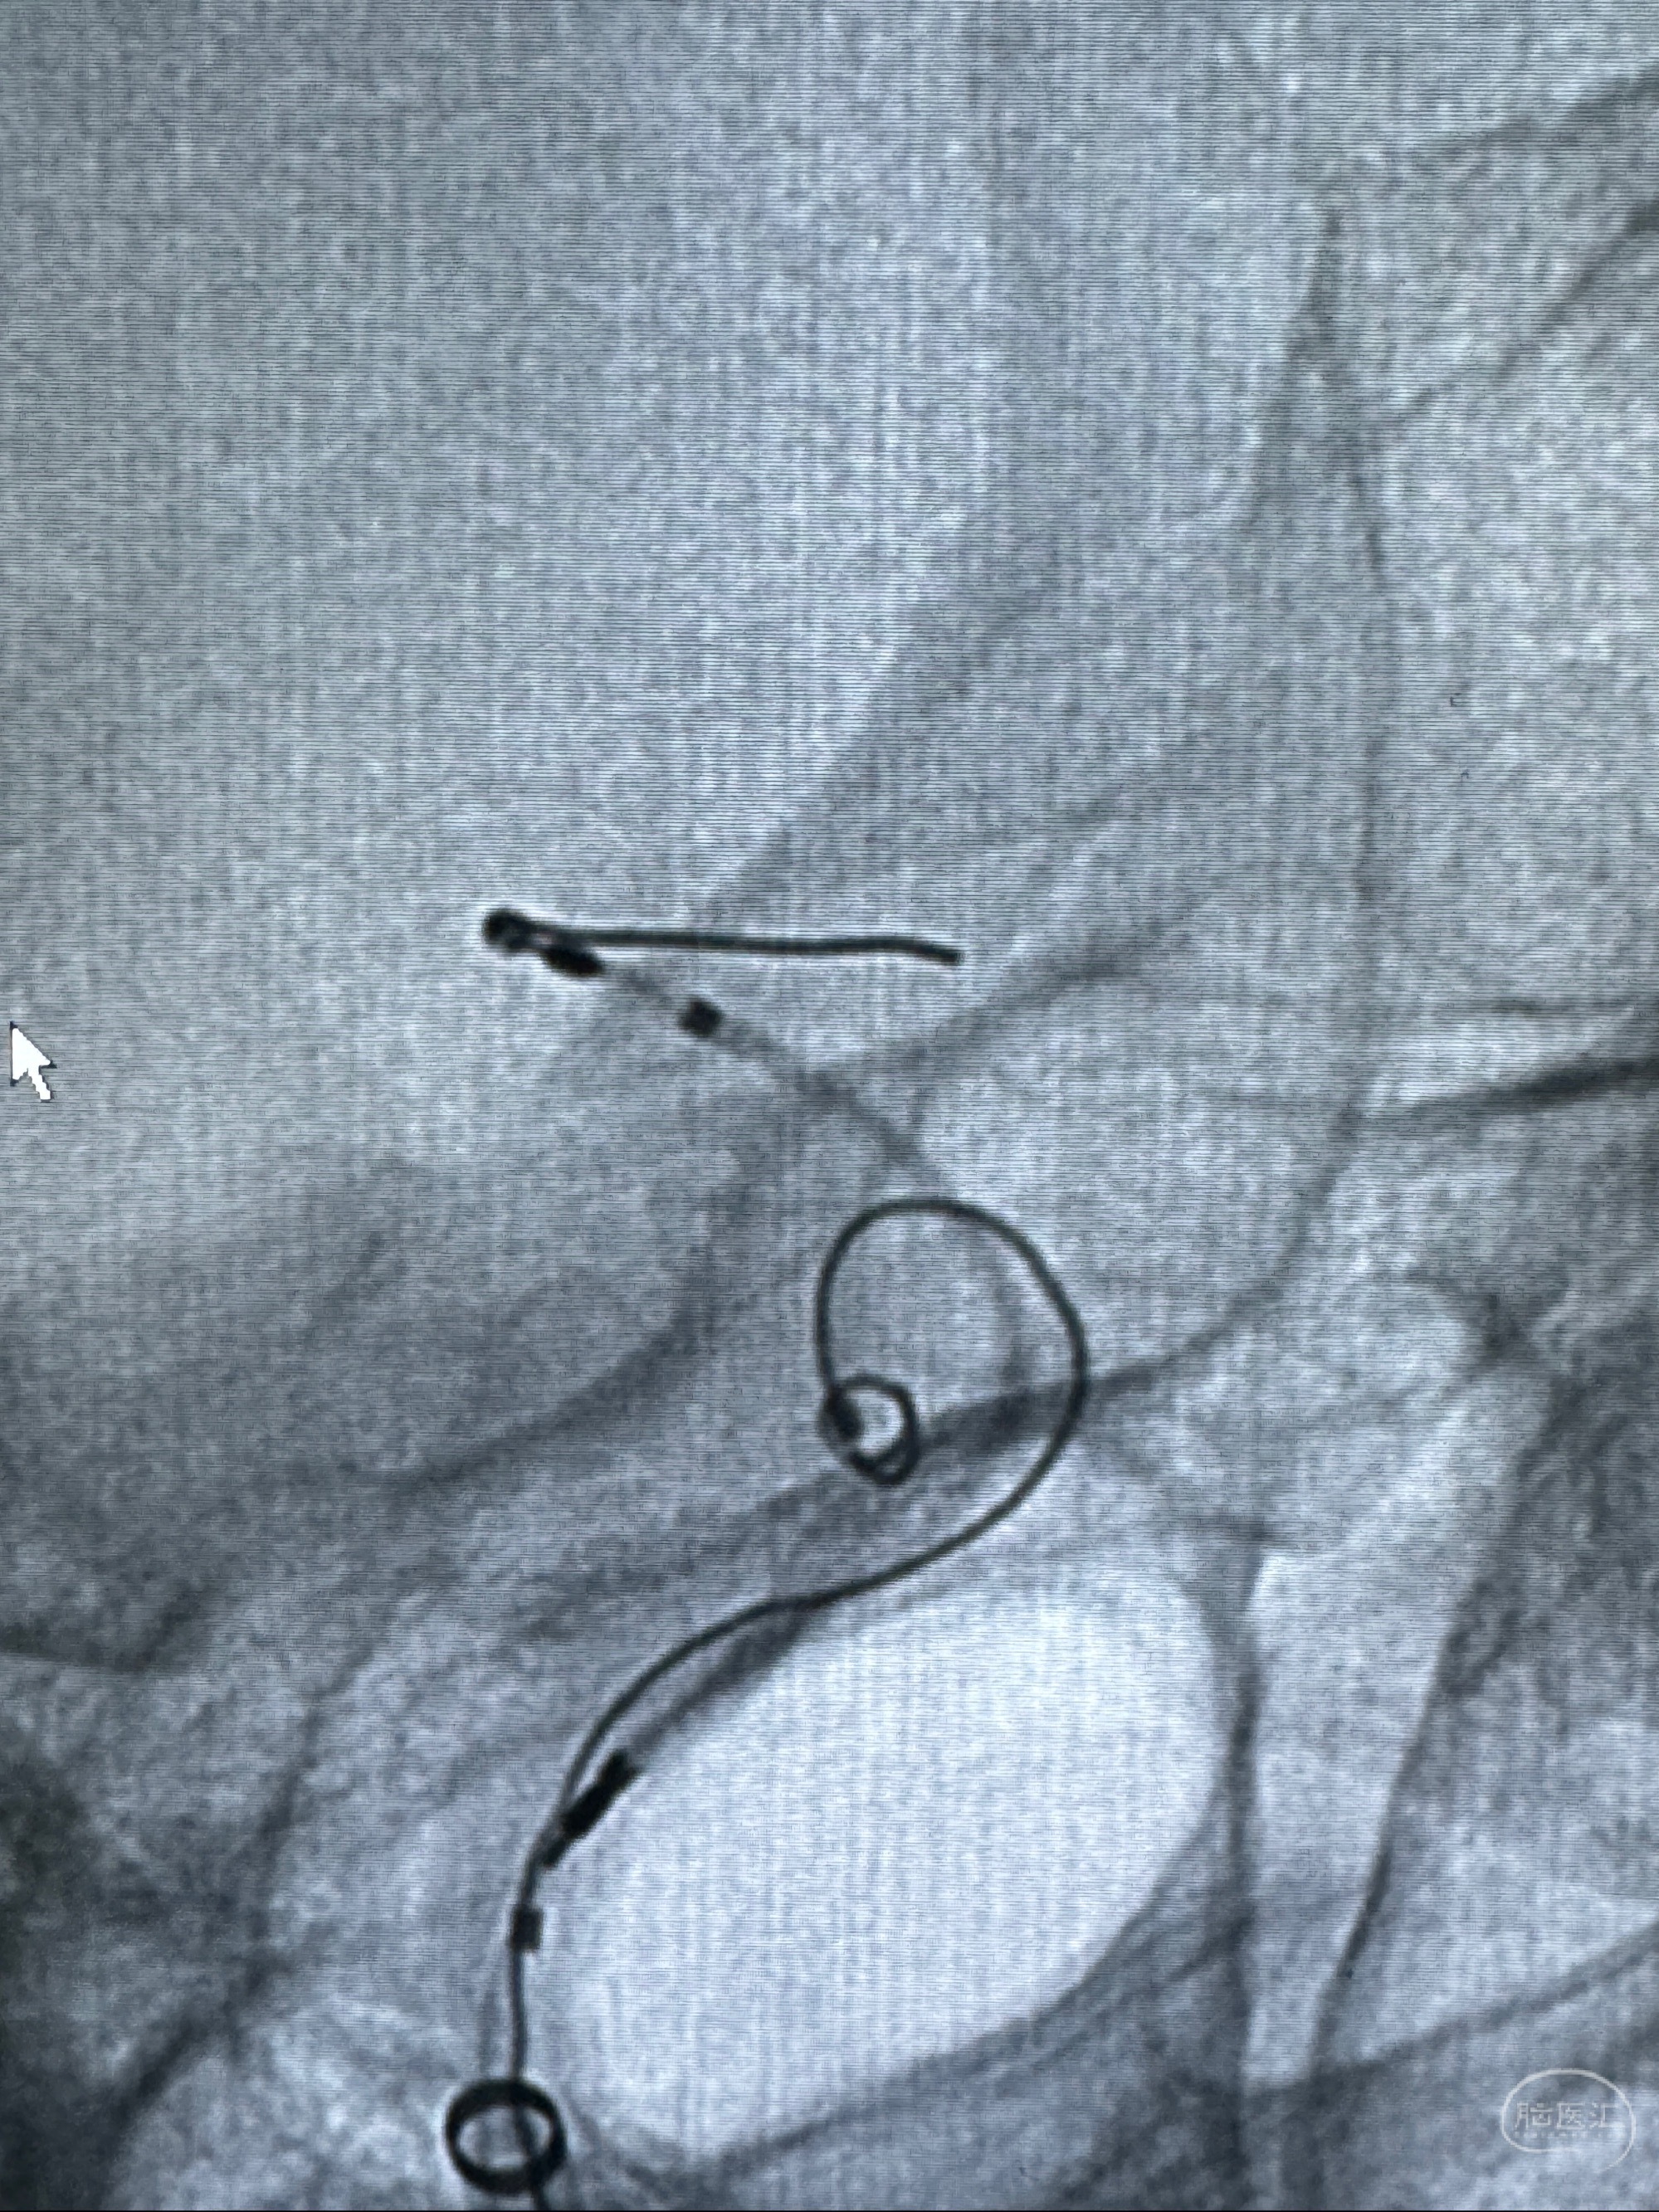

2023-11-29全麻下行NeuroformEZ4.5-20mm支架辅助栓塞

麻醉苏醒佳,遵嘱动作

术后即刻CT